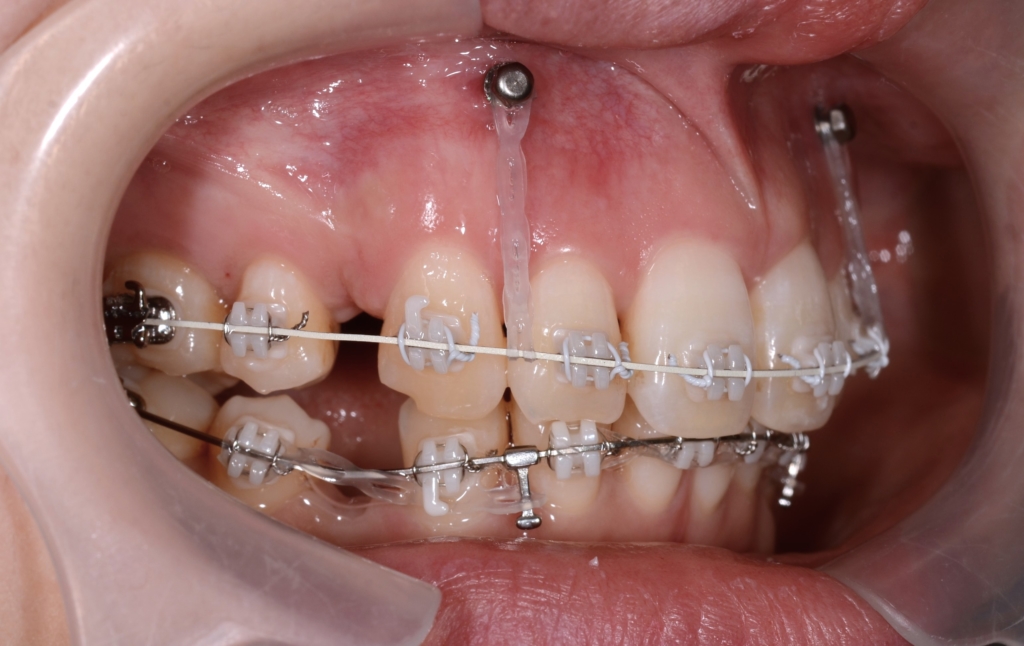

上の前歯が並んだので、ガミースマイルを改善させるために、前歯部にアンカースクリューを植立して準備を整えます。

同じ内容の治療をしている方のモノをイメージ写真として挙げています。

先ずは、その準備として上顎の口蓋にアンカースクリューを追加で植立します。

口蓋のアンカースクリューにPLAS&パラタルバーをセットして、上の歯列全体を後方へ移動させます。